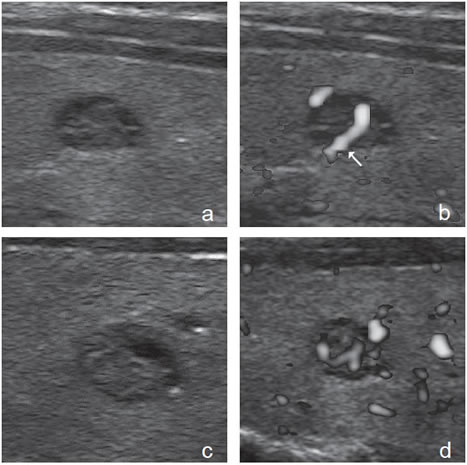

Figura 13. a) Cáncer papilar sólido,

con vascularización central (flecha) con

vasos intranodulares desorganizados;

b) Cáncer papilar sólido delimitado por

vasos periféricos y un vaso central penetrante

de mayor tamaño (flecha); c)

Nódulo coloideo con un patrón de flujo

mixto, periférico y vasos centrales desorganizados

(flechas) que simulan un

patrón maligno; d) Hiperplasia folicular

que muestra un nódulo bien delimitado

con vascularización aumentada,

central y periférica